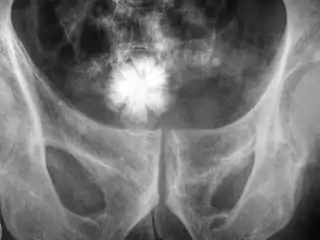

![]() Radiografía de la pelvis con un cálculo en forma de estrella en la vejiga urinaria. | ||

- Radiografía: Una placa radiográfica tradicional del área pélvica, riñones y vejiga es por lo general suficiente para localizar los cálculos urinarios.